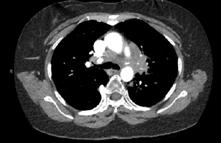

CASE PRESENTATION

A 58-year-old female with recently diagnosed COVID-19 pneumonia was found to have a dry cough and dyspnoea in the setting of persistent bilateral hilar and mediastinal lymphadenopathy associated with bilateral nodular infiltrates. Of note, she immigrated to the USA from India 10 years prior, with the most recent travel to India 2 years ago. Quantiferon testing upon return to the USA was negative at that time. Workup included bronchoscopy with endobronchial ultrasound revealing non-caseating granulomas with negative stains for acid-fast bacilli (AFB). She was diagnosed with Stage 3 sarcoidosis and initiated on prolonged steroid taper with improvement of symptoms. With taper of steroid dose, however, she developed lymphocyte-predominant exudative effusion with negative cultures, and was reinitiated on a protracted steroid course with rapid symptom resolution. At 4-month follow-up, she had worsening CT findings upon steroid taper, and was started on azathioprine. One month later, she required hospital admission for worsening dyspnoea and fatigue. She was noted to be febrile, tachycardic, and tachypnoeic with worsening

hypoxia. Subsequent CT chest showed progression of bilateral nodular infiltrates with new right upper lobe consolidation and air bronchograms concerning for multifocal pneumonia (Figure 1). Incidentally, she was also noted to have calcified splenic granulomas. She developed rapid clinical deterioration, ultimately requiring mechanical ventilation, pressor support, and continuous renal replacement therapy. Repeat bronchoscopy revealed diffuse alveolar haemorrhage with multiple AFB smears positive for Mycobacterium tuberculosis. She was immediately initiated on quadruple therapy, but unfortunately, despite treatment, developed refractory shock and passed away 2 weeks after initial presentation.

TB and sarcoidosis share synonymous manifestations, making differentiating between progression of sarcoidosis and the development of TB difficult, especially in patients who have biopsy-proven sarcoidosis. This patient’s initial negative Quantiferon testing and AFB stains, CT scan findings, pathology, and rapid symptom resolution with steroids support the initial diagnosis of sarcoidosis. Given her history and no recent identifiable risk factors, TB was lower on the differential at initial presentation to the hospital. While findings of lymphocytepredominant pleural effusions3 and splenic granulomas may be seen with sarcoidosis, this should raise suspicion for tuberculosis

A) Initial adenopathy with peripheral patchy ground glass opacities in the right lung following COVID-19 pneumonia. B) Persistent bulky adenopathy 1 year after initial presentation. C) Extensive nodularity throughout the right lung with increasing confluent opacities in the right upper lobe and stable mediastinal lymphadenopathy 2 years after initial presentation. D) Tuberculosis superimposed on sarcoidosis with progression of nodular infiltrates, worsening right upper lobe consolidation, and air bronchograms with incidental calcified splenic granulomas (not pictured).

Figure 1: CT progression of patient’s sarcoidosis and tuberculosis.

and prompt further investigation. This case highlights diagnostic challenges and the need to keep TB on the differential in patients with previous risk factors, despite negative testing and progressive CT findings with biopsyproven sarcoidosis.